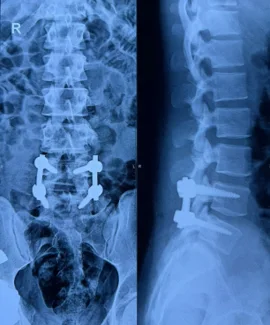

Before & After Clinical Gallery

We showcase real patient cases (with consent), including:

• Pre- and Post-operative MRIs and X-rays

• Disc Herniations, Stenosis, and Spondylolisthesis cases

• Visible improvement in alignment and decompression

Before

After